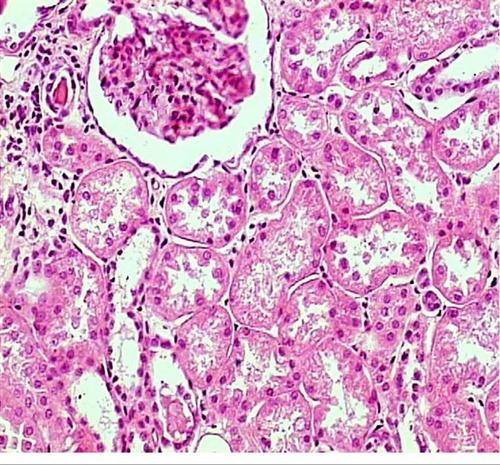

慢性肾小球肾炎是以蛋白尿、血尿、高血压、水肿为主要临床表现。

刻诊:下肢水肿,小便不利,腰酸困痛,口渴,倦怠乏力,舌质淡红,苔薄白,脉沉弱。检查显示,尿蛋白(+++)。辨为肾虚不化证,治当益气温阳、渗利水气。给予栝楼瞿麦丸与防己黄芪汤合方加味:天花粉12g,茯苓20g,山药20g,附子10g,瞿麦6g,防己3g,白术12g,黄芪15g,生姜12g,大枣1枚,炙甘草2g。6剂,水煎服,每日1剂,每日3服。二诊:腰酸困痛减轻,以前方6剂。三诊:下肢水肿减轻,以前方6剂。四诊:小便通利,以前方6剂。五诊:

倦怠乏力好转,以前方6剂。六诊:下肢水肿消退,检查尿蛋白(+),以前方6剂。之后,为了巩固疗效,以前方60余剂治疗,经复查尿蛋白(-),又以前方变汤剂为散剂,每次6g,每日3服。随访1年,一切尚好。

【用方提示】根据腰酸困痛、小便不利辨为肾虚不化,再根据下肢水肿辨为水气内停,因倦怠乏力辨为气虚,以此辨为肾虚不化证。方以栝楼瞿麦丸益气温肾、利水消肿;以防己黄芪汤健脾制水、发散水气;加大黄芪用量以益气利水化水。方药相互为用,以奏其效。